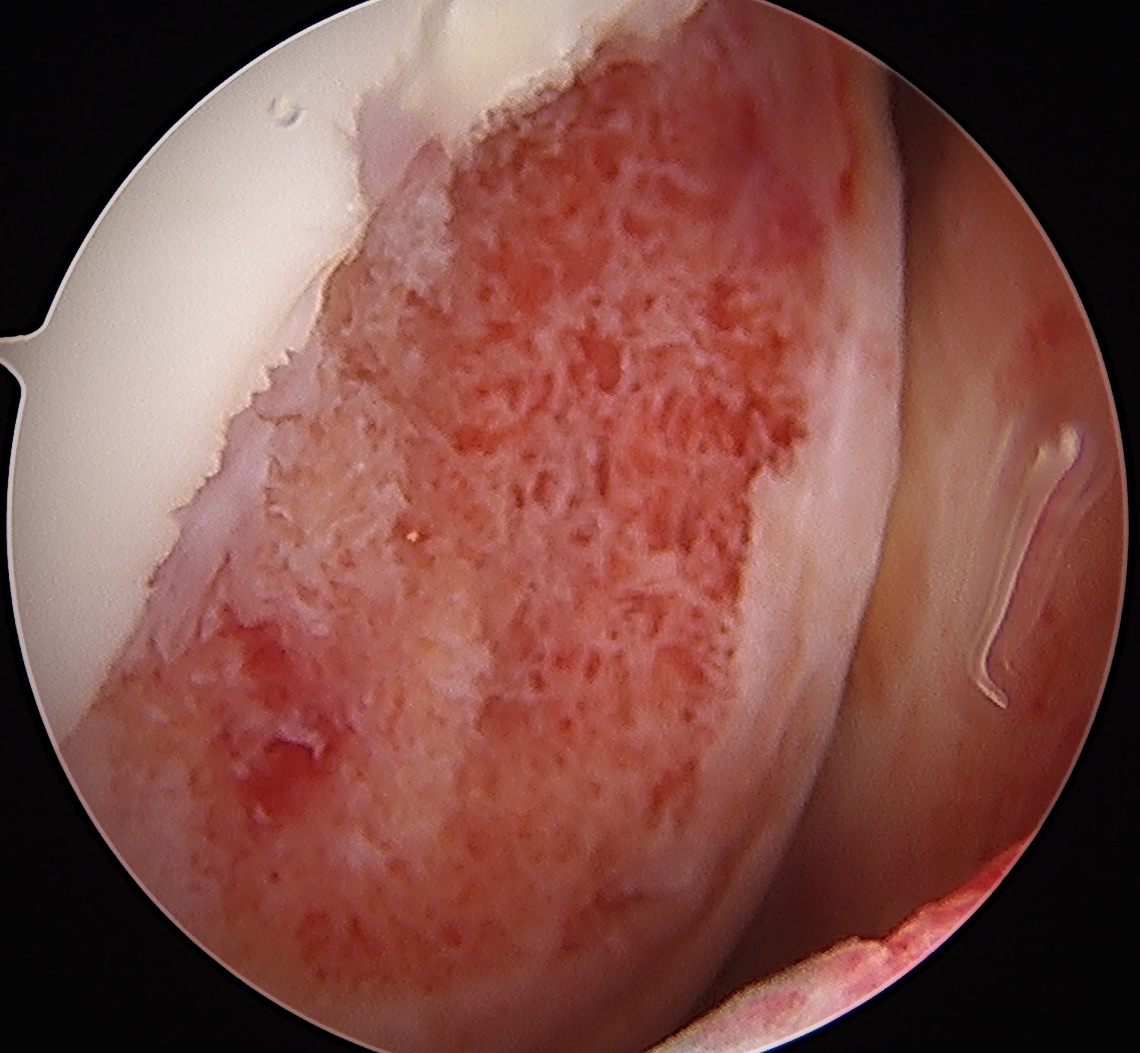

Grade 1: Softening and swelling of the cartilage

Grade 2: Partial thickness defect < 1.5 cm in diameter

Grade 3: Fissuring to subchondral bone, > 1.5 cm in diameter

Grade 4: Exposed subchondral bone

Issue - focus on size of cartilage lesion rather than depth

ICRS / International Cartilage Research Society Arthroscopy Classification

Grade I: Nearly normal - soft indentation / superficial fissures and cracks

Grade II: Abnormal - cartilage lesions < 50% of cartilage depth

Grade III: Severely abnormal - cartilage lesions > 50% of cartilage depth

Grade IV: Severely abnormal - cartilage lesion down to subchondral bone

Grade 0 / normal

Grade I: soft cartilage, superficial fissures

Grade II: cartilage lesion < 50%

Grade III: cartilage lesion > 50%

Grade IV: cartilage lesion down to subchondral bone